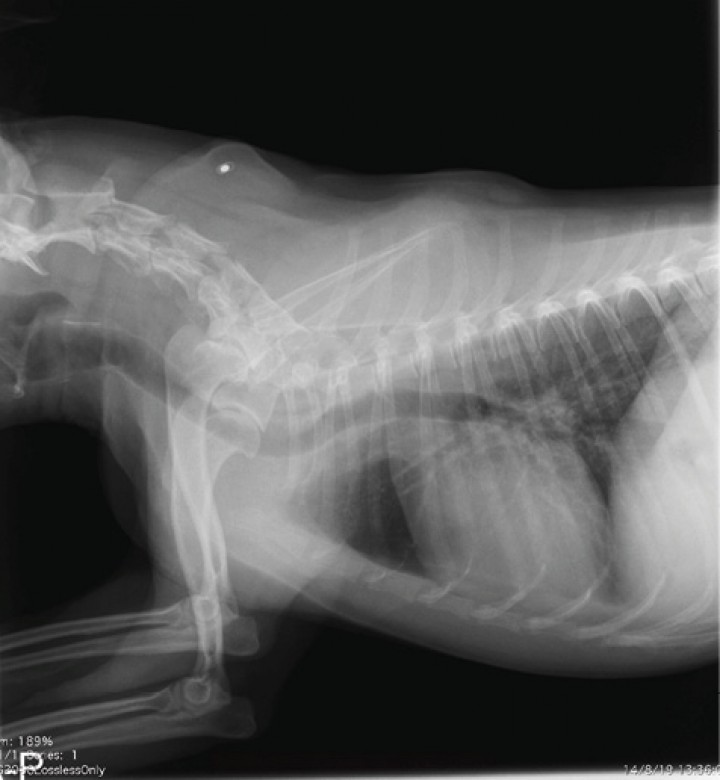

Acude de urgencias a consulta un Yorkshire terrier macho castrado de 13 años de edad y 2 kilos de peso. Tras un episodio de estrés en su clínica de referencia, el animal comenzó a ladrar y “llorar” observándose una grave dilatación en la zona ventral del cuello, la cual aparecía con cada gemido. En la exploración realizada en el Hospital Clínico Veterinario de la Universidad de Extremadura, todas las constantes se encuentran dentro de la normalidad y no se observan anomalías en el cuello ni en la entrada del tórax a la palpación y presión traqueal, incluso tras provocarle la tos. No hay historial de traumatismos ni problemas respiratorios previos. No se observan anomalías relevantes en la hematología y bioquímica completa. Nos remiten una radiografía de cráneo y cuello latero-lateral derecha (Fig. 1) y se realiza a su llegada al HCV de la UEx una radiografía torácica latero-lateral derecha de tórax (Fig. 2).

<p>Proyección latero-lateral derecha de la región cervical incluida la cabeza. Imagen cedida por la Clínica Veterinaria Azureus.</p>

Proyección latero-lateral derecha de la región cervical incluida la cabeza. Imagen cedida por la Clínica Veterinaria Azureus.